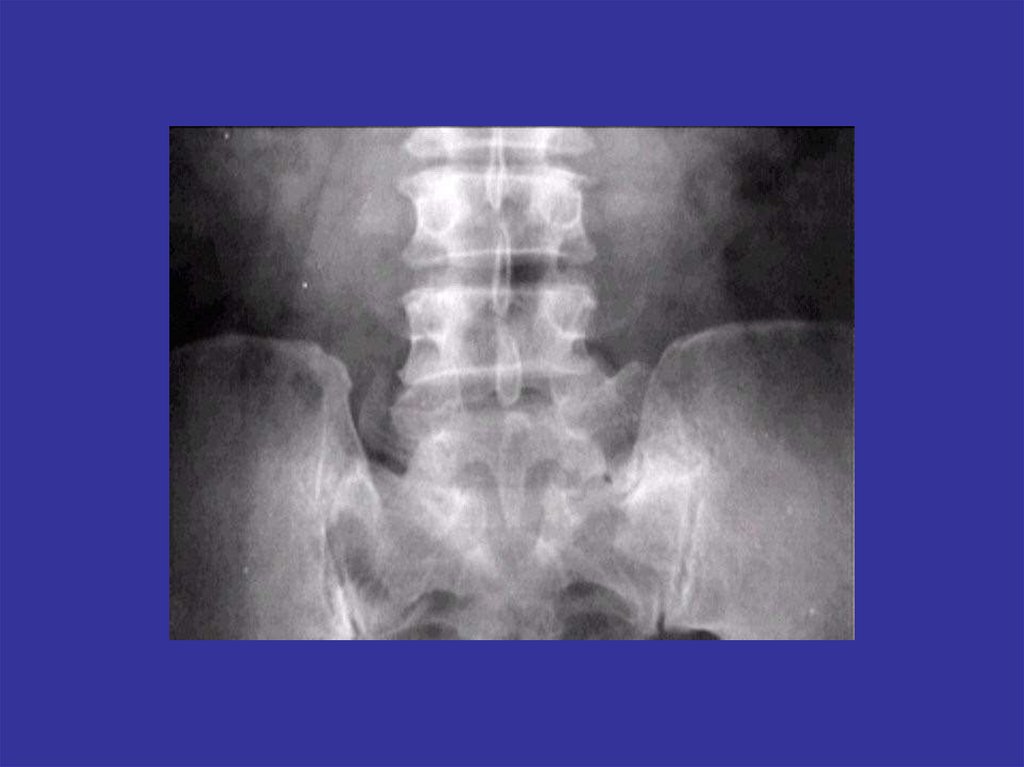

Аномалии развития позвоночника